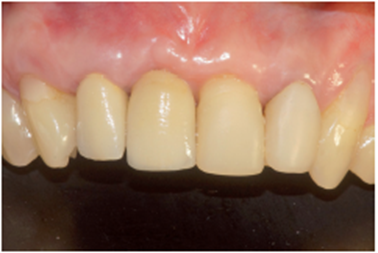

Após a conclusão desses passos pelo laboratório, a prótese do elemento 12 foi cimentada com fosfato de zinco e a prótese sobre o pilar Ideale foi parafusada e torqueada a 10 Ncm (Figura 36). O orifício de acesso foi restaurado com resina fotopolimerizável (Figura 37). Uma radiografia final foi realizada, demonstrando o perfeito assentamento da coroa sobre o pilar Ideale.

No presente caso clínico, existia perda óssea causada pela lesão apical. A implantação imediata com o posicionamento adequado aproveitando a maior quantidade de remanescente ósseo foi realizada associada ao enxerto com biomaterial de origem bovina e membrana de PTFE-d. A escolha pela reabilitação com coroa protética parafusada só foi possível devido a utilização do pilar angulado da linha Ideale de 30 graus.

A implantação imediata, com regeneração óssea guiada, associada a utilização do pilar angulado da linha Ideale, mostrou-se uma alternativa viável de tratamento neste caso, viabilizando a confecção de prótese parafusada em região de pré-maxila com extensa lesão periapical, proporcionando resultados funcionais e estéticos satisfatórios.